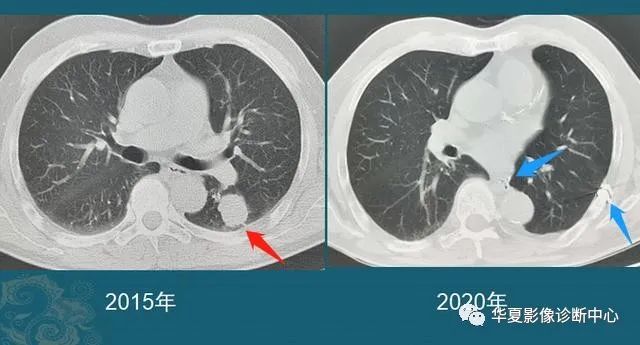

最后给大家看几个手术成功的肺结节,有个直径超过3 cm,已经属于肿块了(红箭头是肿瘤,蓝箭头是手术瘢痕):

病例2,男性,75岁,体检发现左肺结节,2.9 cm,左肺下叶切除5年(病理类型不详,在外院手术,家属只记得是肺癌,不能描述具体类型,看肿瘤形态,鳞癌、腺癌都有可能):

图9